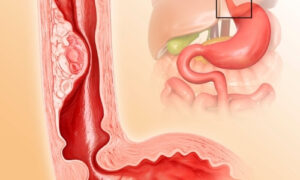

سرطان المريء هو مجموعة الخلايا التي تبدأ النمو في المريء. المريء أنبوب مجوف طويل يصل بين الحلق والمعدة. ويساعد المريء على نقل الطعام الذي تبتلعه